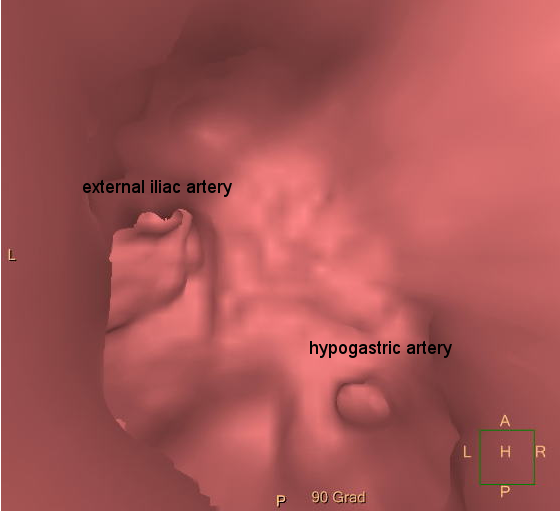

I opted for a transbrachial recanalization of the left hypogastric artery. With the pre-procedural CT-scans a 3D-reconstruction of the iliac bifurcation was performed. With these pictures it is possible to simulate an inravascluar view. This perspective revealed the origin of the occluded hypogastric artery with a small deepening. This is exactly the location where you can anchor your guidewire during the intervention.